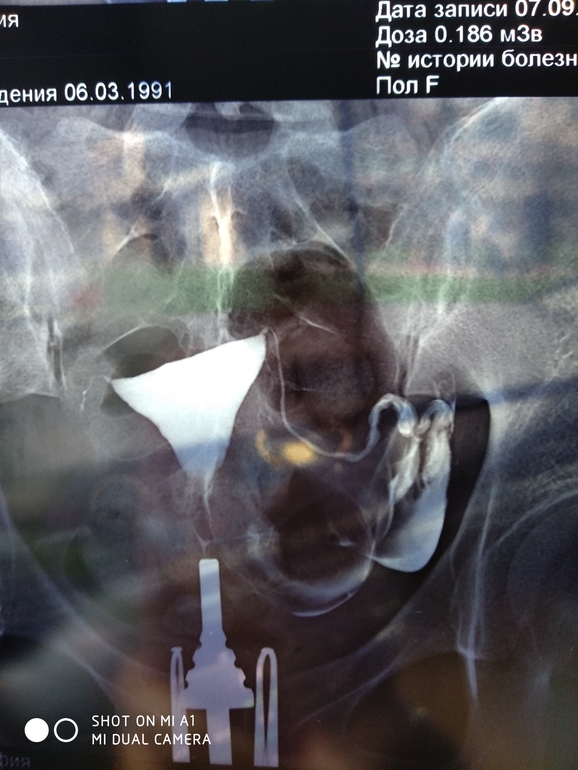

Снимок после ГСГ

Кто разбирается,вдруг у кого так было,это действительно очень тонкая труба??

Ещё говорят спаечный процесс

Если трубу видно на снимке значит она не проходима

Почему? У меня тоже на снимках было видно трубы, но они проходимы.

Это значит в них задерживается жидкость. А это значит либо они извиты и жидкость с трудом выходит, либо не проходимы. Ну либо это спазм. Вообще эта процедура малоинформативна.

Мне кажется наоборот,если есть отрезок где не видно жидкость,то этот отрезок и не проходим

Лена, вы уж извините, но вы чушь пишете. смешали обычное узи с проверкой труб. это на обычном узи если видно трубу, то это не хорошо. А на рентгене если видно полностью трубу с жидкостью выходящей, то это очень хорошо. по поводу малоинформативности, так это 50/50. не ложиться второй раз на лапару. а здесь как раз в некоторых случаях процедура является стимулом к наступлению гестации, так как контрастная жидкость приводит к смыванию деривата, закупоривающего трубы. А также она разъединяет тонкие сращения и активизирует работу бахромки, захватывающей и продвигающей яйцеклетку (это я с одного сайта за гсг взяла).

Ничего я не смешала. Я тоже делала такую процедуру. И вот на снимке та, труба которая вроде как была не проходима как раз и визуализировалась.

И вот тут как раз про мало информативность. Такая процедура очень часто даёт ложно отрицательный результат, из-за спазма. И если её и делать то под наркозом.

У меня на этой процедуре одна из труб была вообще не проходима. А на лапаре обе трубы: "аж со свистом проходимы" Это дословно слова хирурга.

А вам сактосальпинкс не ставят слева?

Правая труба,муж говорит, непроходима.

Добрый день. Извините, но почему оставшееся труба не проходима? с нее же контраст вышел. и я не вижу сактосальпинкс

Может я неверно выразилась. Частично непроходима.скорее всего контраст задерживается в трубе,так как просвечивается вся труба. И очень большая вероятность внематочной беременности. А сактосальпинкс - это расширение на конце трубы в ампулярном отделе. Вы доктор?

я не врач, но с отношением врачей к пациентам, я наверно и пойду на врача сдавать. можно с вами поспорить? только не обижайтесь, я просто хочу для себя понять. труба на конце всегда расширенна и может быть так что когда фотографировали, то была жидкость продолжала вытекать с матки, матка же тоже видно. я за все время просмотрела столько снимков и отзывов девочек. и при таком снимке девочки чудесно беременели. Хотя в России сейчас для большинства доступна программа ЭКО по полюсу. и можно сделать прчину трубный фактор и спокойно идти на ЭКО. Для меня с моим местом жительства эта программа не доступна.

Да,возможно Вы правы. Смотря на какой минуте после введения контраста был сделан снимок.

Сейчас посмотрела ваши посты,поняла,что трубу удалили,оказывается. Муж и говорит мне,что вначале немного прослеживается,а потом не идет контраст,а я с ним спорю,что не удаляли трубу вам😑

Да,в мае удалили правую,ВБ была

Не хотела писать негатив,но муж говорит, что шансов очень мало забеременнеть с такой трубой. Говорит,что сактосальпинкс с большой вероятностью присутствует и что она частично непроходима. Извините,если расстроила.

Он специалист лучевой диагностики: рентген, кт и мрт. Именно он проводит и смотрит в таких случаях как у автора ГСГ и делает заключение о проходимости,состоянии труб.